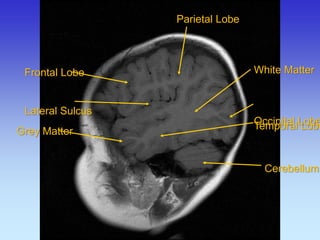

Grey Matter

White Matter

Occipital Lobe

Cerebellum

Frontal Lobe Lateral Sulcus

Parietal Lobe

Temporal Lobe